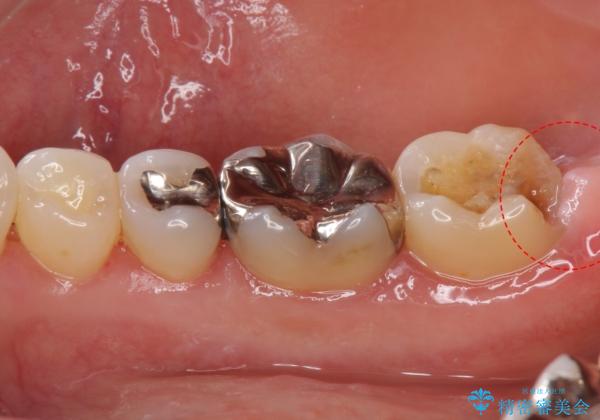

- 詰め物が外れたから作り直しをしたいとのことで来院されました。

外れた状態で日にちが経過していたため、まわりの歯ぐきが歯の上に乗っかっている状態です。

歯ぐきの形を整えてから治療をしていきます。

歯ぐきの形を整えることで精度の良い詰め物を入れることができました。